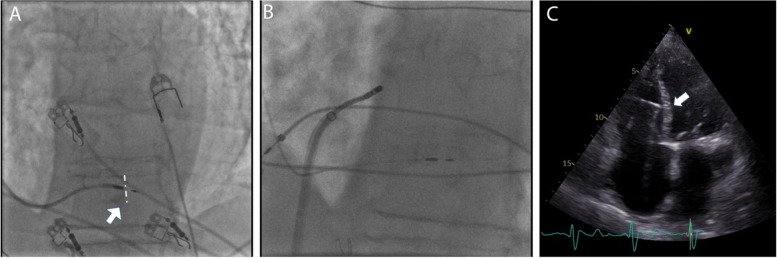

Fig. 3.

Fluroscopic and echocardiographic images of the left bundle branch pacing (LBBP) lead. A LBBP lead in left anterior oblique (LAO) 30-degree fluoroscopic view. A thin layer of contrast can be seen (arrow) outlining the right ventricular septal wall (dashed line), demonstrating the lead depth. B Final ablation target site in relation to the pacing lead. C Echocardiographic image showing the severely enlarged atria and transseptal position of the pacing lead (arrow)

Venography on the left side showed a persistent left superior vena cava (Fig. 2A). A decision was made to attempt LBBAP lead implantation from the right side. To enable SelectSecure 3830 69 cm pacing lead (Medtronic Inc., Minneapolis, MN, USA) positioning and adequate support for transseptal screwing, the delivery sheath C315-HIS (Medtronic Inc., Minneapolis, MN, USA) was manually modified with dilator in place by creating a 90-degree curve at the right subclavian vein-superior vena cava junction. The distance between the reshaping point and the presumed septal region was estimated by placing the sheath on the body surface under fluoroscopy (Fig. 2B). The sheath was then inserted through the guidewire from the right subclavian vein access to the basal part of the RV septum as previously described. Then, in right anterior oblique 200 the pacing lead was inserted into the delivery sheath to find the initial pacing site, where the V1 lead appeared to be W-shaped. The modification of the C315-HIS catheter allowed perpendicular positioning of the lead tip to the interventricular septum in left anterior oblique 300 with minimal torque. The fluoroscopic image of the final pacing lead implantation site can be viewed in Fig. 3A. Subsequently, the lead was gradually screwed transeptally until unipolar pacing at the site showed a right bundle branch block QRS morphology with a notch in the nadir of the QS complex. With the time interval from stimulus to peak of R wave in lead V6 of 80 ms, isoelectric interval on intracardiac electrogram, and the V6-V1 interpeak interval of 50 ms LBB capture was confirmed (Fig. 1C) [3]. Pacing parameters were excellent: R-wave sensing 15.4 mV, threshold 0.75 V at 0.5 ms, and unipolar pacing impedance 646 Ohm. The lead was connected to dual-chamber pacemaker device in the ventricular port, while a pin was inserted in the atrial port (Fig. 2C). Dual-chamber device was selected in case of any additional lead insertion in the future, e.g. in case of sinus rhythm restoration. The total procedural time was 50 minutes and the fluoroscopy time was 7.4 minutes. During and after the procedure the patient reported no chest pain or other adverse events and there were no ST-T changes present on native 12-lead ECG. AV node ablation with non-irrigated ablation catheter was performed the next day (Fig. 3B). The periprocedural LBBAP lead parameters remained stable. Pacemaker was set to VVIR pacing with 80 bpm rest rate (Fig. 1B).

In a short-term follow-up of 6 months, the LBBAP parameters set to bipolar pacing remained stable (threshold 0.75 V at 0.5 ms, impedance 689 Ohm), the mechanical dyssynchrony was no longer present, and the cardiac function improved (LVEF 60%) (Fig. 3C). The patient also reported improved exercise capacity and no signs or symptoms of HF.